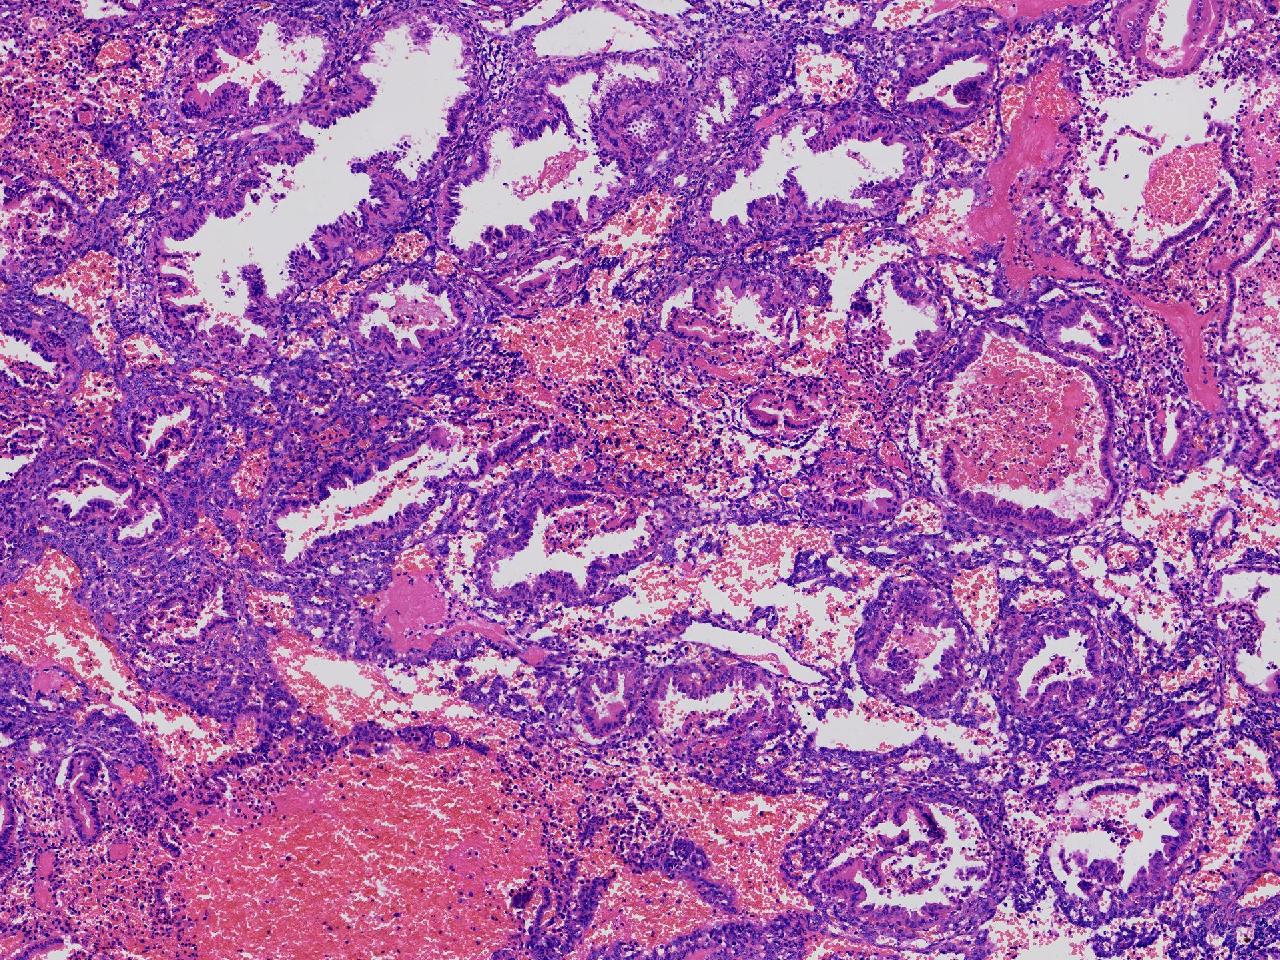

分泌期样改变?

性别

女

年龄

45岁

阴道不规则出血20余天,

彩超示:宫腔内见约41X11毫米的不均质回声区。宫腔镜示:宫腔形态正常,内膜粉红,不规则增厚。

子宫内膜

灰粉色不整形软组织多块,1.5X1X0.6厘米。

分泌反应子宫内膜,伴有出血。

晚泌期及月经早期改变,局部呈啫酸性乳头状化生改变。